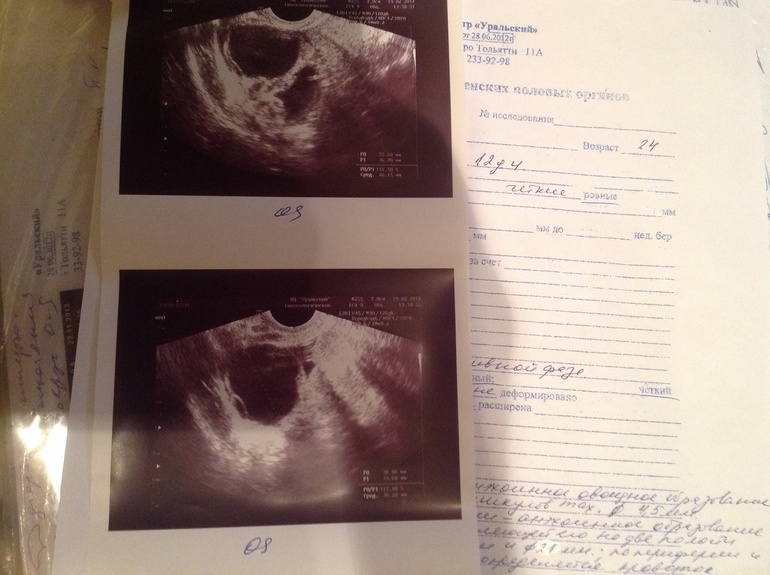

Фотки узи на 2 цикл отмены ок 12 день цикла